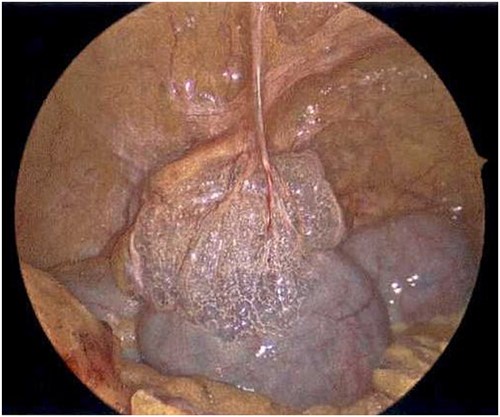

On Hospital Day 2, an interval CXR showed continued resolution of the right-sided pneumothorax but worsening subcutaneous emphysema of the bilateral chest wall and pneumoperitoneum (Fig. 3). Surgical consultation was sought, leading to diagnostic laparoscopy. In the abdomen, emphysematous changes within the gastrohepatic ligament and omental adhesions to the anterior abdominal wall were visualized (Figs 5 and 6). Laparoscopic exploration revealed no diaphragmatic injury or perforated viscera but identified emphysematous changes throughout the preperitoneal space, small and large bowel mesentery, and right paracolic gutter (Figs 7 and 8). Immediate post-op CXR no longer showed evidence of pneumoperitoneum (Fig. 4). The patient was transferred back to the ICU and extubated after three days on Day 5. After the removal of chest tube and transfer to a medical floor on Day 8, the patient developed aspiration pneumonia that was treated with antibiotics. She was discharged on Day 15.

Laparoscope of the right paracolic gutter revealing emphysematous changes of the mesentery.